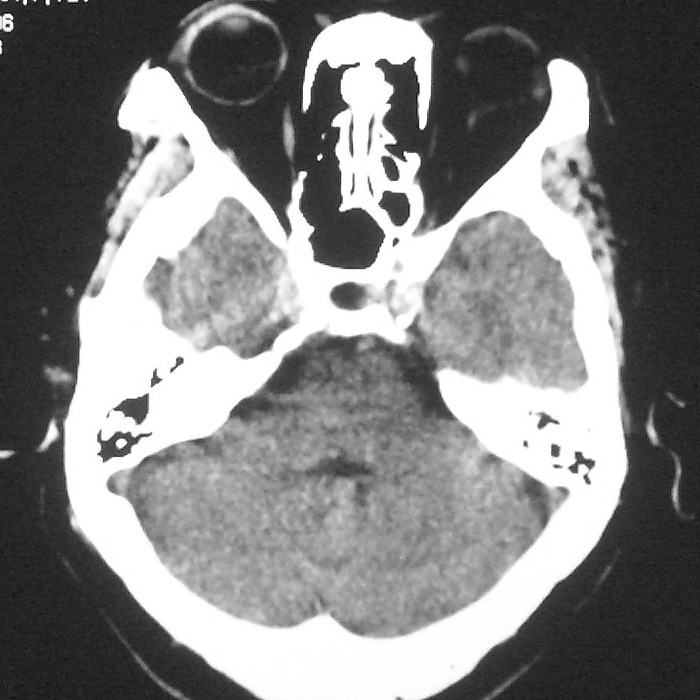

左侧半卵圆中心腔梗应当比较明确,右侧基底节好象不明显,不好说,做个mri明确吧

右侧基底,左侧半卵圆中心腔梗

1、右侧基底,左侧半卵圆中心腔梗。2脑萎缩。

左侧半卵圆中心,右侧基底节腔梗。再加个脑萎缩吧